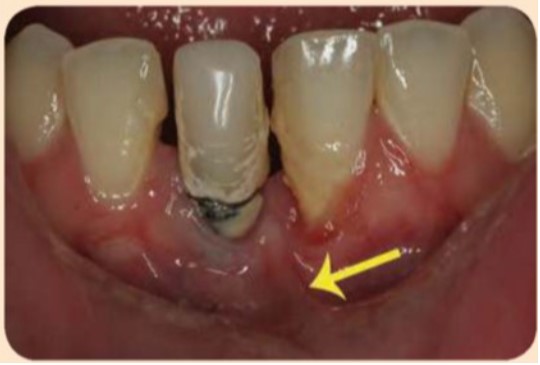

Có sự tích tụ mảnh vụn thức ăn và mảng bám quanh các implant. Tháo phục hình trên implant #45 và #46 cho thấy hoàn toàn không có nướu sừng hóa mặt ngoài (hình dưới đây).

Thiếu nướu sừng hóa ở mặt ngoài quanh implant càng thấy rõ hơn sau khi tháo phục hình trên implant.

Implant #41 có chiều rộng nướu sừng hóa rất ít và bị bao phủ bởi mảng bám và vôi răng. Thắng bám sai chỗ ở phía gần của implant #41 (mũi tên màu vàng) có thể cản trở việc kiểm soát mảng bám hiệu quả.